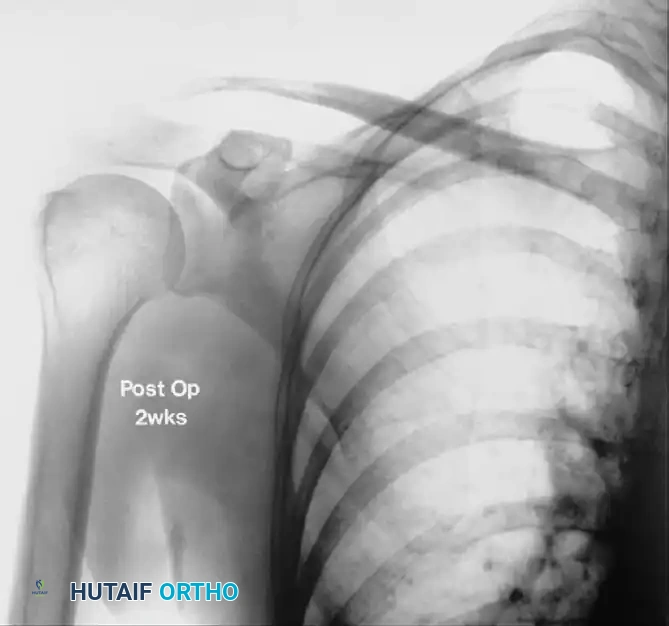

FIGURE 46-13 B: Radiograph taken 2 weeks after arthroscopic excision, demonstrating complete resolution of the calcific deposit and restoration of the subacromial interval.